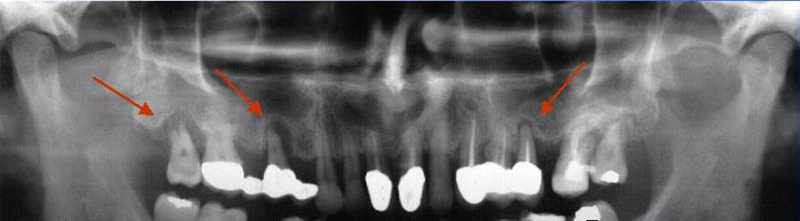

Periometr - první plně automatizovaný přístroj pro zjištění periodontálního statusu pacienta - diagnózy, léčby a profylaxe parodontitidy a dalších onemocnění. Díky správnému určení periodontálnímu statusu pacienta lze včas odhalit a minimalizovat objevující se obtíže.

Používá se i v implantologii, při stanovení diagnózy a léčby periimplantitidy (zánětu měkkých tkání a kosti v okolí implantátu).